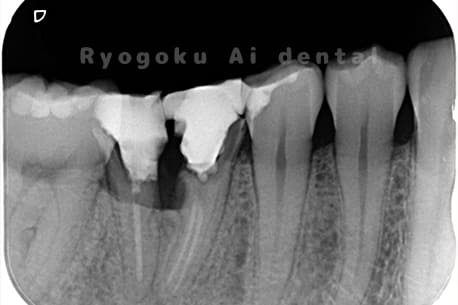

他院で右下の根の治療を行い、セラミックを被せる説明をされていたが、根の治療が終わらないため転院された患者さんです。隣の親知らずの抜歯の必要性と、根の治療を行なっている歯牙の予後が悪いため、移植治療を提案し、右下の親知らずの抜歯と同時に、右下の奥歯(7番)への移植治療を行いました。被せ物を行う必要もなく、順調に経過してます。